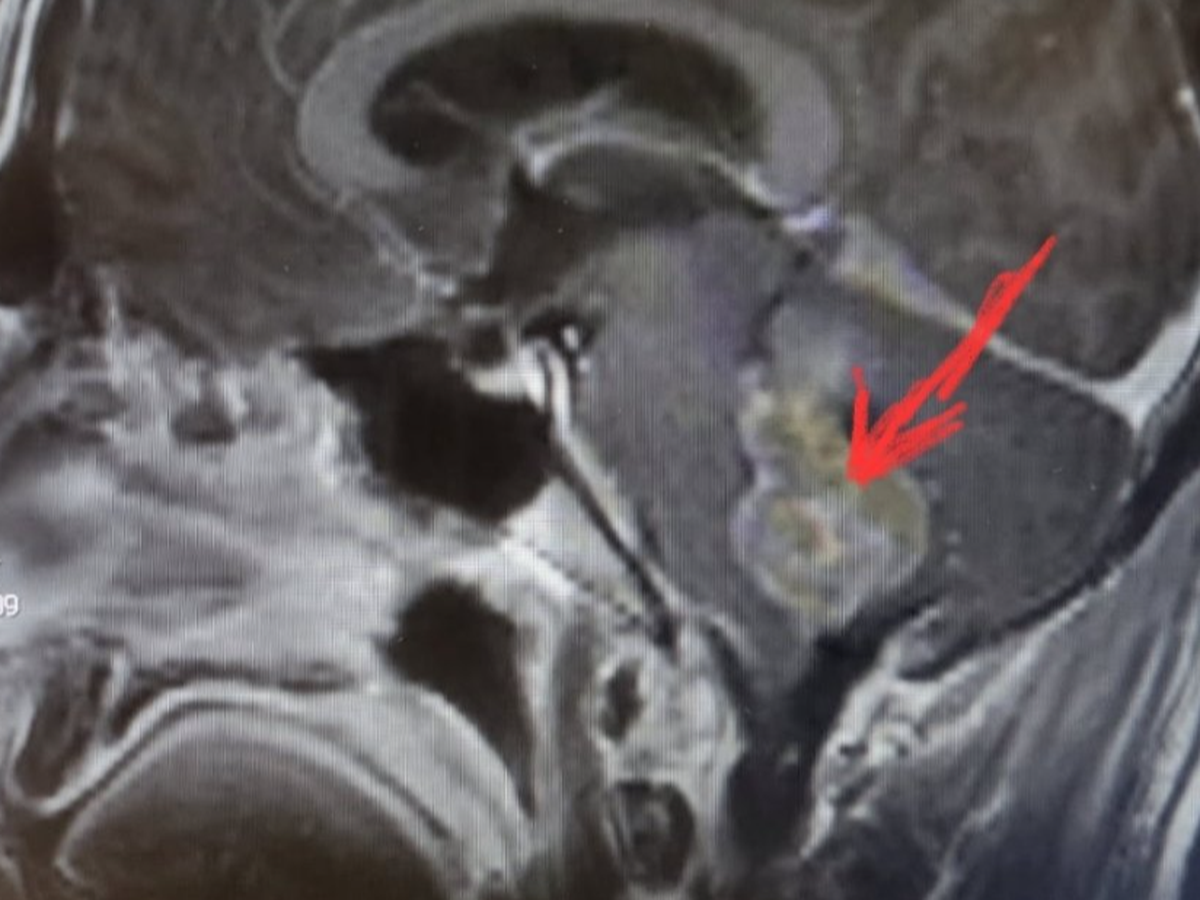

I’m reaching out to ask for help for my brother, Stepan, who recently underwent emergency brainstem surgery. While we are incredibly grateful that the surgery was successful, his journey to recovery is going to be long, challenging, and filled with uncertainty.